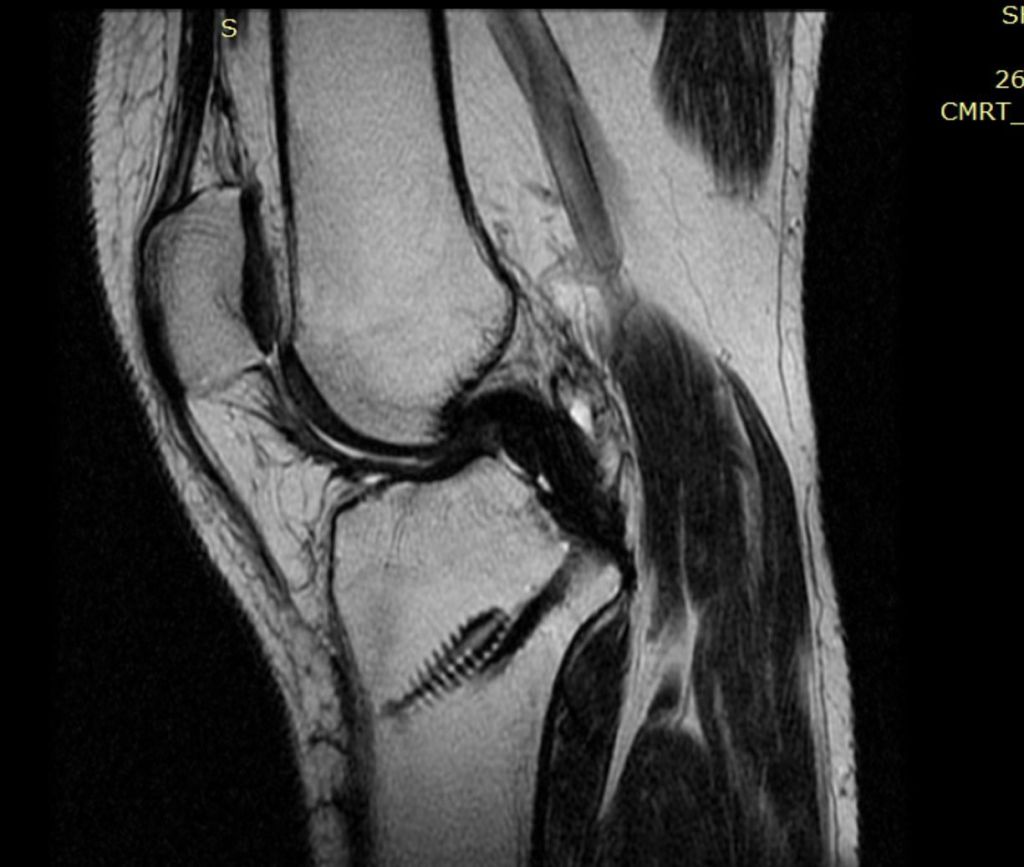

Николай Николаевич доктор которого я знаю давно, он очень хороший человек, внимательный, профессионал своего дела, всегда на связи не смотря на свой загруженный график и большое количество пациентов. В 2016 году у сестры мужа была травма коленного сустава, позвонили Николай Николаевичу, заочно дал консультацию, сказал что делать, сделали МРТ приехали... Ещё Николай Николаевич доктор которого я знаю давно, он очень хороший человек, внимательный, профессионал своего дела, всегда на связи не смотря на свой загруженный график и большое количество пациентов. В 2016 году у сестры мужа была травма коленного сустава, позвонили Николай Николаевичу, заочно дал консультацию, сказал что делать, сделали МРТ приехали к нему, после осмотра и консультации назначил день операции по поводу пластики передней связки коленного сустава. Все было четко и грамотно, сестра очень боялась, но доктор настроил положительно!Операция прошла хорошо, после была реабилитация и восстановление, он координировал нас, результат был отличным, до сих пор колено не подводит!)спасибо)

В 2022 году обратились к Николай Николаевичу уже с мужем, тоже травма коленного сустава только уже порвал задний крест, все так же МРТ , консультация и вот мы уже готовимся к операции! Прошло все быстро, муж четко соблюдал все рекомендации следовал всем предписаниям , реабилитация и вот он так же быстро восстановился и вернулся к активному образу жизни, занимается спортом- велосипед, бег, зал- колено как новое, не беспокоит, а главное стабильное! Мы довольны! Спасибо огромное за лечение, за его волшебные руки, я рекомендую этого специалиста, как человека и профессионала- проверено годами))))

Фото после пластики ЗКС

Фото к отзыву о Гнелица Николай Николаевич